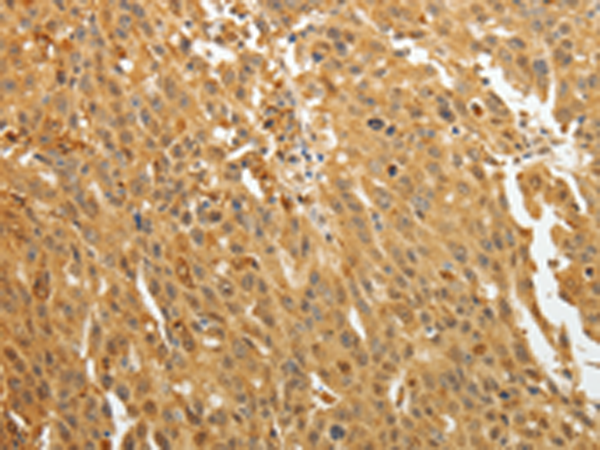

分类: 科研抗体货号: P11178别名: AR; ADR; ALR2; ALDR1应用: WB,IHC反应种属: Human